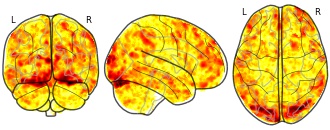

Individual Brain Charting dataset extension, second release of...

- neurovault.org

niftiUpdated Feb 14, 2020 Share

EmailClick to copy linkLink copied Cite(2020). Individual Brain Charting dataset extension, second release of high-resolution fMRI data for cognitive mapping: sub-04_ses-21_task-self_dir-pa_run-02_recognition_other_hit [Dataset]. http://identifiers.org/neurovault.image:364869niftiAvailable download formatsUnique identifierhttps://identifiers.org/neurovault.image:364869Dataset updatedFeb 14, 2020License

Cite(2020). Individual Brain Charting dataset extension, second release of high-resolution fMRI data for cognitive mapping: sub-04_ses-21_task-self_dir-pa_run-02_recognition_other_hit [Dataset]. http://identifiers.org/neurovault.image:364869niftiAvailable download formatsUnique identifierhttps://identifiers.org/neurovault.image:364869Dataset updatedFeb 14, 2020LicenseCC0 1.0 Universal Public Domain Dedicationhttps://creativecommons.org/publicdomain/zero/1.0/

License information was derived automaticallyDescriptionCollection description

The individual Brain Charting (IBC) Project is using high resolution fMRI to map 13 subjects that undergo a large number of tasks: the HCP tasks, the so-called ARCHI tasks, a specific language task, video watching, low-level visual stimulation etc. The native resolution of the data is 1.5mm isotropic. Their main value lies in the large number of contrasts probed, the level of detail and the high SNR per subject. This dataset is meant to provide the basis of a functional brain atlas. We upload here smoothed individual SPMs. The uploaded maps comprise session-specific and fixed effects across maps acquired with AP and PA phase encoding directions.

Note that Neurovault collection #4438 is a subset of that one. In the present collections, some details have been fixed, including mroe accurate and unique file naming.

Subject species

homo sapiens

Modality

fMRI-BOLD

Analysis level

single-subject

Cognitive paradigm (task)

Self evaluation task

Map type

Z

- N